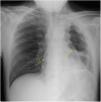

The chest radiography showed signs of pneumopericardium (Figure 1, long yellow arrows) and left cavitary lung mass. For better characterization, the patient underwent a computed tomography lung scan which revealed the extension (from the apex to the diaphragmatic surface) of the thick-walled gas-filled mass (Figure 2A/B, short black arrow) with an air-fluid level (Figure 2B, long black arrow) and distension of pericardial cavity with air-fluid level (Figure 2A/B, long yellow arrow) due to a direct pleuro-pericardial communication.